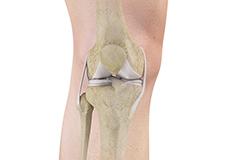

Knee Anatomy

The knee is a complex joint made up of different structures - bones, tendons, ligaments, and muscles. They all work together to maintain the knee’s normal function and provide stability to the knee during movement. Having a well-functioning healthy knee is essential for our mobility and ability to participate in various activities.